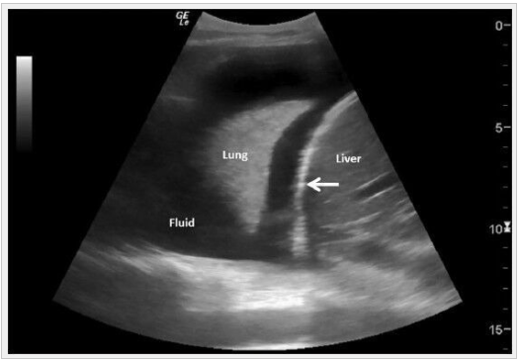

What is shown here?

Pleural Effusion

What is blue arrow pointing to?

US of Spnt Pneumo showing absence of sliding lung